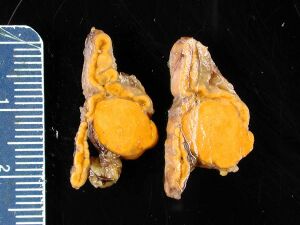

| ورم غدي كظري في مريض مصاب بمتلازمة كون | |

نظرًا لطبيعتها غير المصحوبة بأعراض ، تم التعرف على معظم الحالات المبلغ عنها من أورام الغدة الكظرية الغدية مصادفة من خلال تشريح الجثة أو أثناء التصوير الطبي ، وخاصة التصوير المقطعي المحوسب والتصوير بالرنين المغناطيسي . ومن ثم ، فقد حصلوا على عنوان الورم العرضي الذي يشير إلى ورم غدي صغير تم اكتشافه بالمصادفة..[10] على الرغم من أن أورام الغدة الكظرية الغدية تعتبر تحديًا للتمييز عن قشرة الغدة الكظرية الطبيعية ، إلا أنها تظهر على أنها آفات مقيدة جيدًا بمجرد عزلها..[بحاجة لمصدر]

وصف إجمالي

- آفة متحددة جيدًا

- حجم ≤5 سم

- الوزن ≤ 50 جرام

- غالبًا ما تظهر ككتلة ذات لون أصفر ذهبي

(قد يكون لها مناطق داكنة بؤرية تتوافق مع النزف ، ونضوب الدهون ، وليبوفوسين))[10]